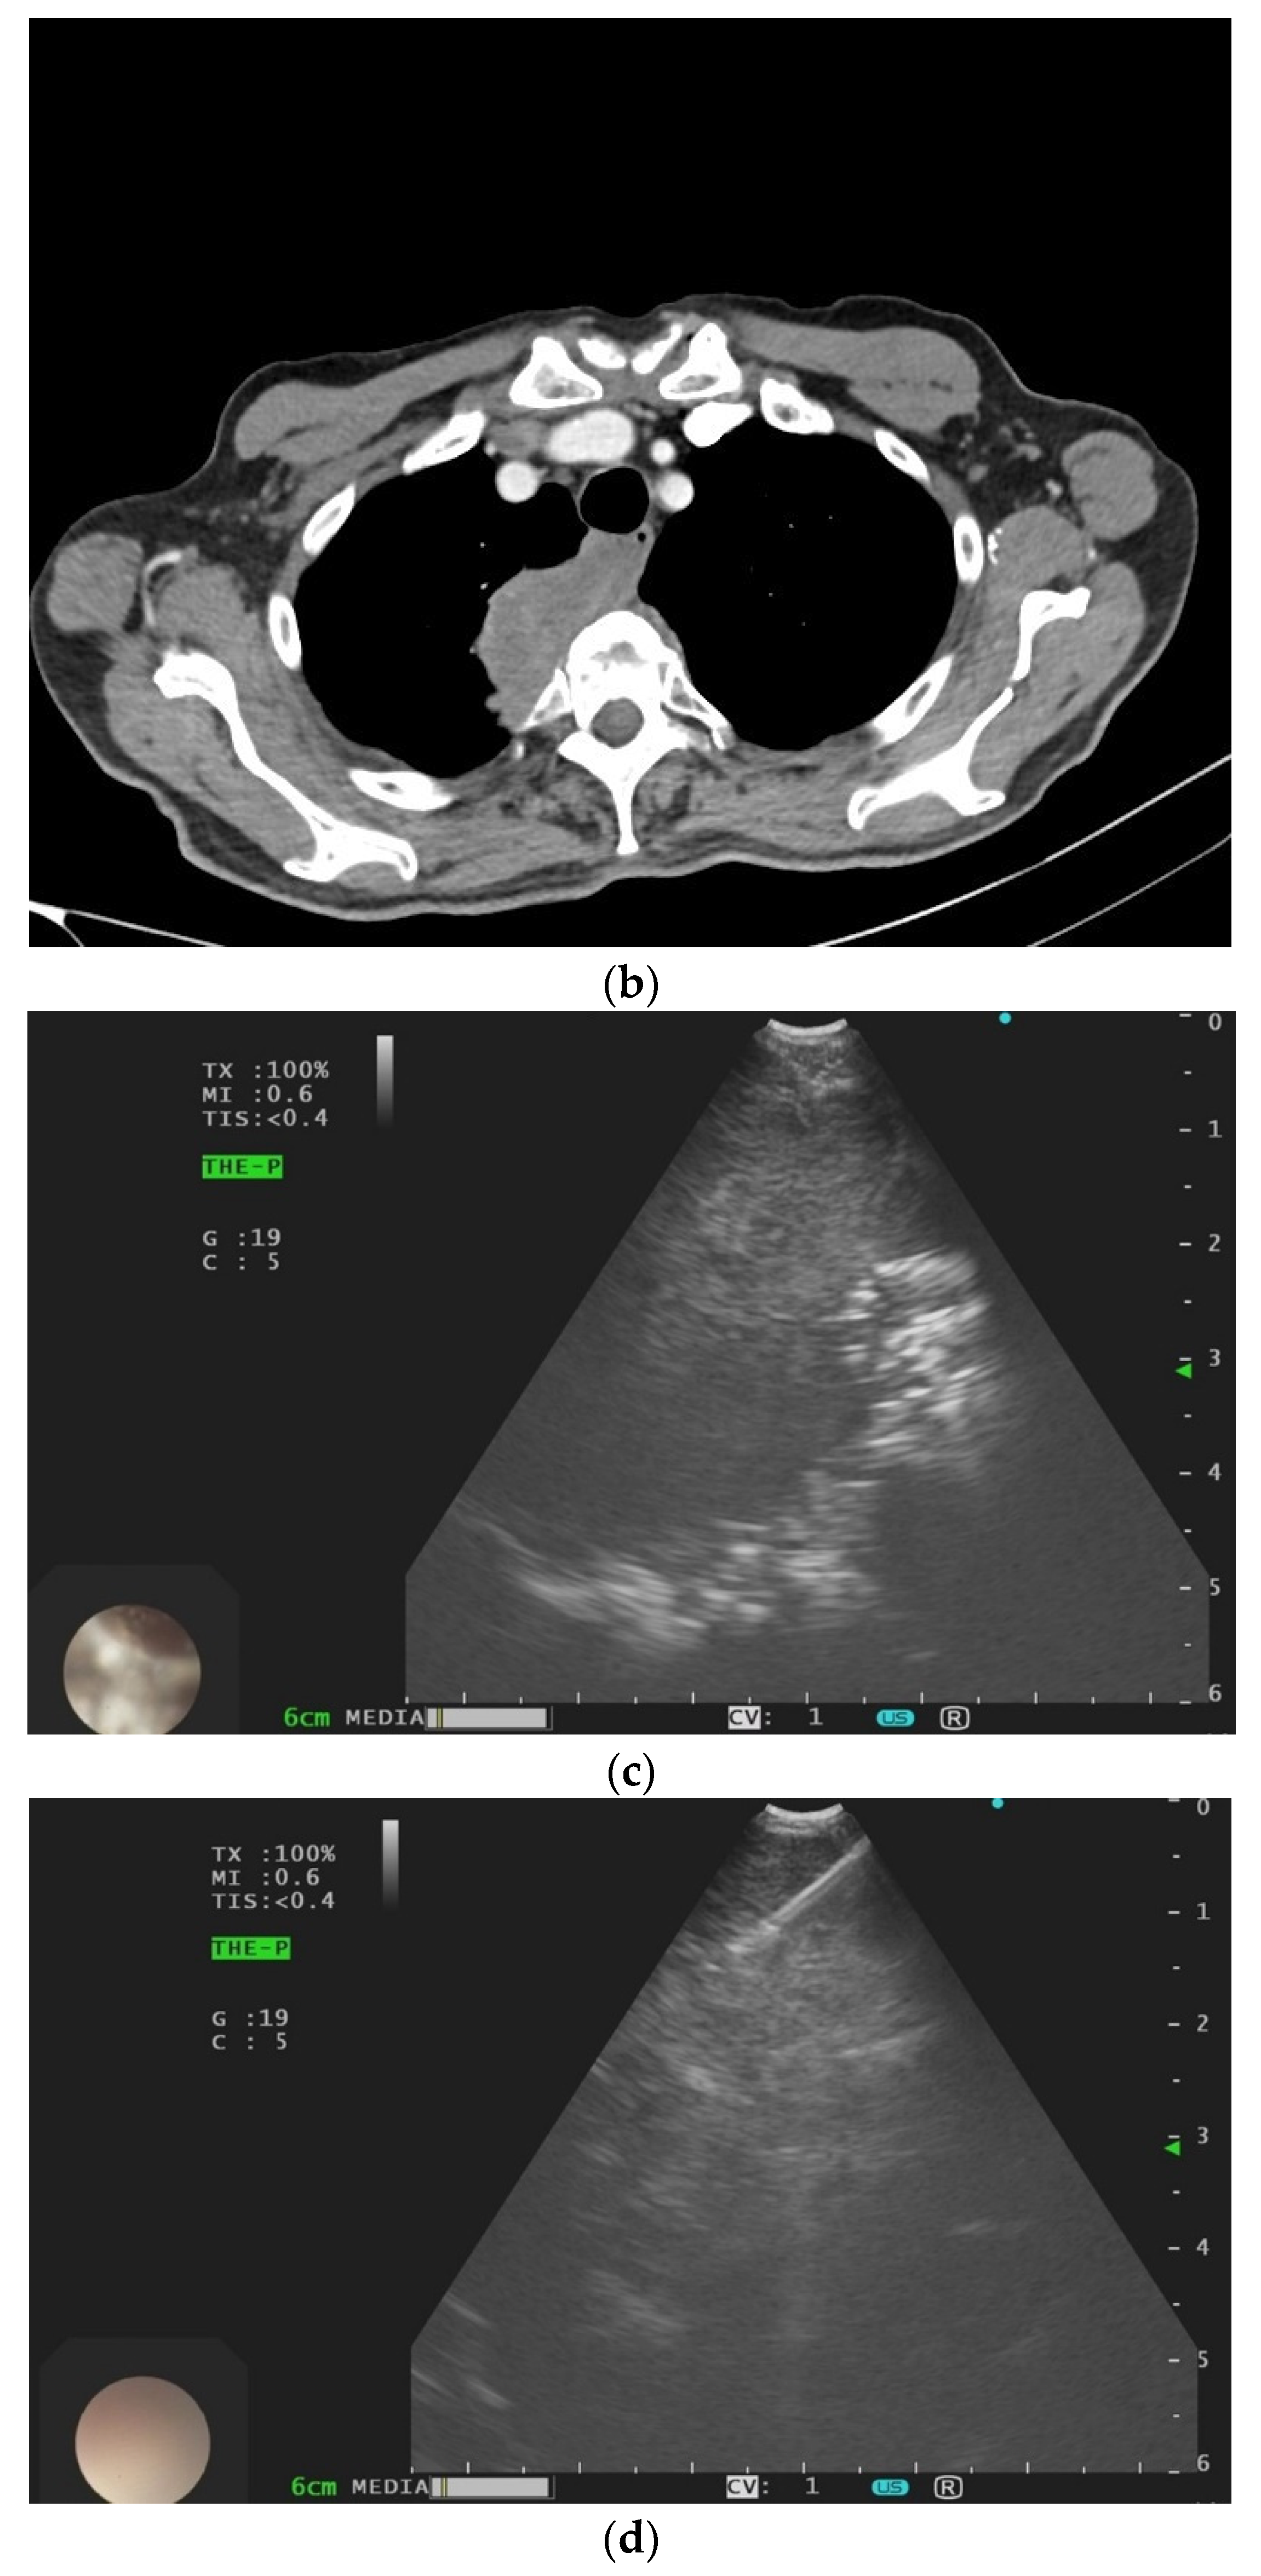

2. Primary Pulmonary Sarcomas